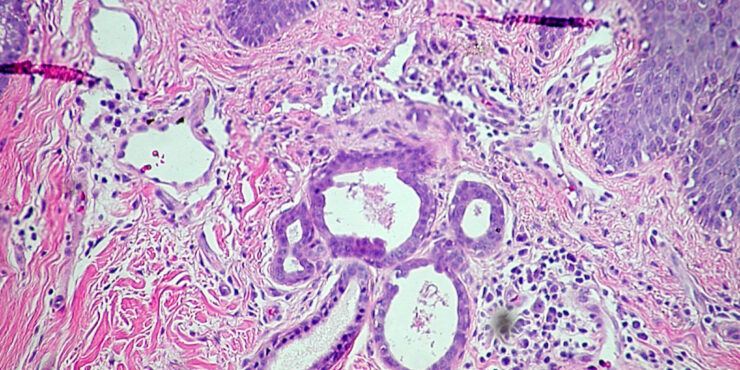

Read MoreNevus_comedonicus = الوحمة الزؤانية Nevus Comedonicus A nevus comedonicus consists of closely set, slightly elevated papules that have in their center a dark, firm, hyperkeratotic plug resembling a comedo. Nevus comedonicus, like linear epidermal nevus, usually has a linear configuration and occurs as a single lesion. In some instances, however, there are multiple bilateral linear […]